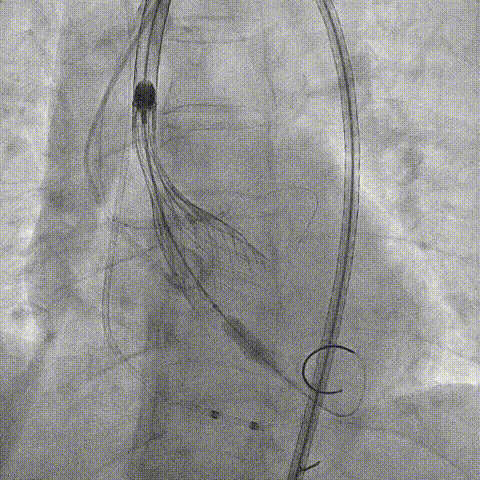

再次评估左冠开口,考虑调整瓣膜深度

回收后调整深度,再次释放

评估左冠开口

左冠开口切线位造影

决定左冠烟囱支架保护冠脉

调整支架位置

释放冠脉支架

释放瓣膜

造影评估

支架内后扩张

冠脉造影

根部造影